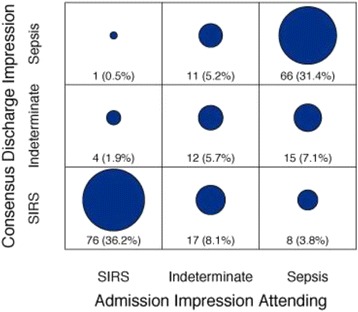

P035 - Challenges in the clinical diagnosis of sepsis

R. Miller III, B. K. Lopansri, L. C. McHugh, A. Seldon, J. P. Burke